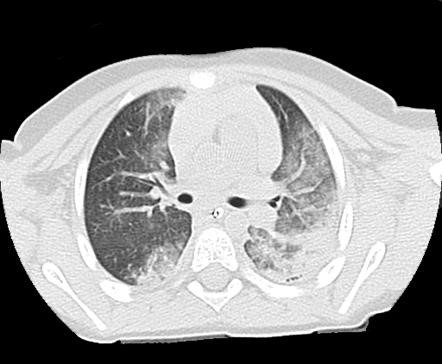

Ağciyər əzilməsi

Kiçik ölçülü əzilmə və hematomalar klinik asimptomatik ola bilər, ağciyəri geniş əhatə edən böyük əzilmələr isə klinik olaraq hipoksiya əlamətləri ilə büruzə verir. Diaqnozu rentgenlə və KT ilə dəqiqləşdirilir. Hipoksiya əlamətləri olanlarda mexaniki ventilyasiya və bronxial tualet tövsiyə olunur (Şəkil 2).

Şəkil 2. Ağciyər əzilməsi